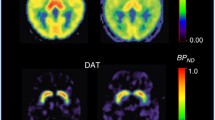

The mean plasma concentration-time profiles after single dose oral and i.v. administration of d-phenylglycine-l-dopa and l-dopa are depicted in Figure 4. The pharmacokinetic parameters calculated with the data of plasma concentration-time curves based on the non-compartmental model analysis were summarized in Table 2. The fraction of oral absorption (BA) was calculated according to Equation 1. The Striatal dopamine level after i.v. injection of d-phenylglycine-l-dopa (50 mg/kg) is depicted in Figure 5.

Striatal dopamine level after i. v. injection of d -phenylglycine- l -dopa. Values represent the group mean ± s.e.m. (n = 4). Single dose d-phenylglycine-l-dopa (50 mg/kg in 2.5 mL of normal saline) was administered i.v. via femoral vein to anesthetized male Sprague-Dawley rats (280 - 320 g). The dialysates collected from the brain microdialysis probe was subjected to HPLC to measure the striatal dopamine concentration at 10 min interval.

The striatal dopamine level increased gradually after i.v. injection of d-phenylglycine-l-dopa and had not reached plateau 3.5 hours when the anaesthetized mice woke up. The gradual release of dopamine in brain striatum rendered this dipeptide as a dopamine sustained-releasing prodrug.